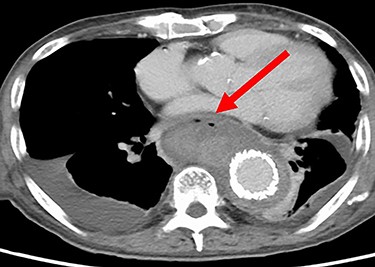

Seven days after TEVAR, the patient developed fever, and a CT scan showed bilateral iliopsoas abscesses and gas images inside the aneurysm (Fig. 2). We decided to perform upper gastrointestinal endoscopy and CT-guided drainage for abscesses. Endoscopy showed perforation of the esophageal wall and accumulation of necrotic tissue (Fig. 3).

CT seven days after TEVAR. Arrow shows gas images inside the aortic aneurysm.